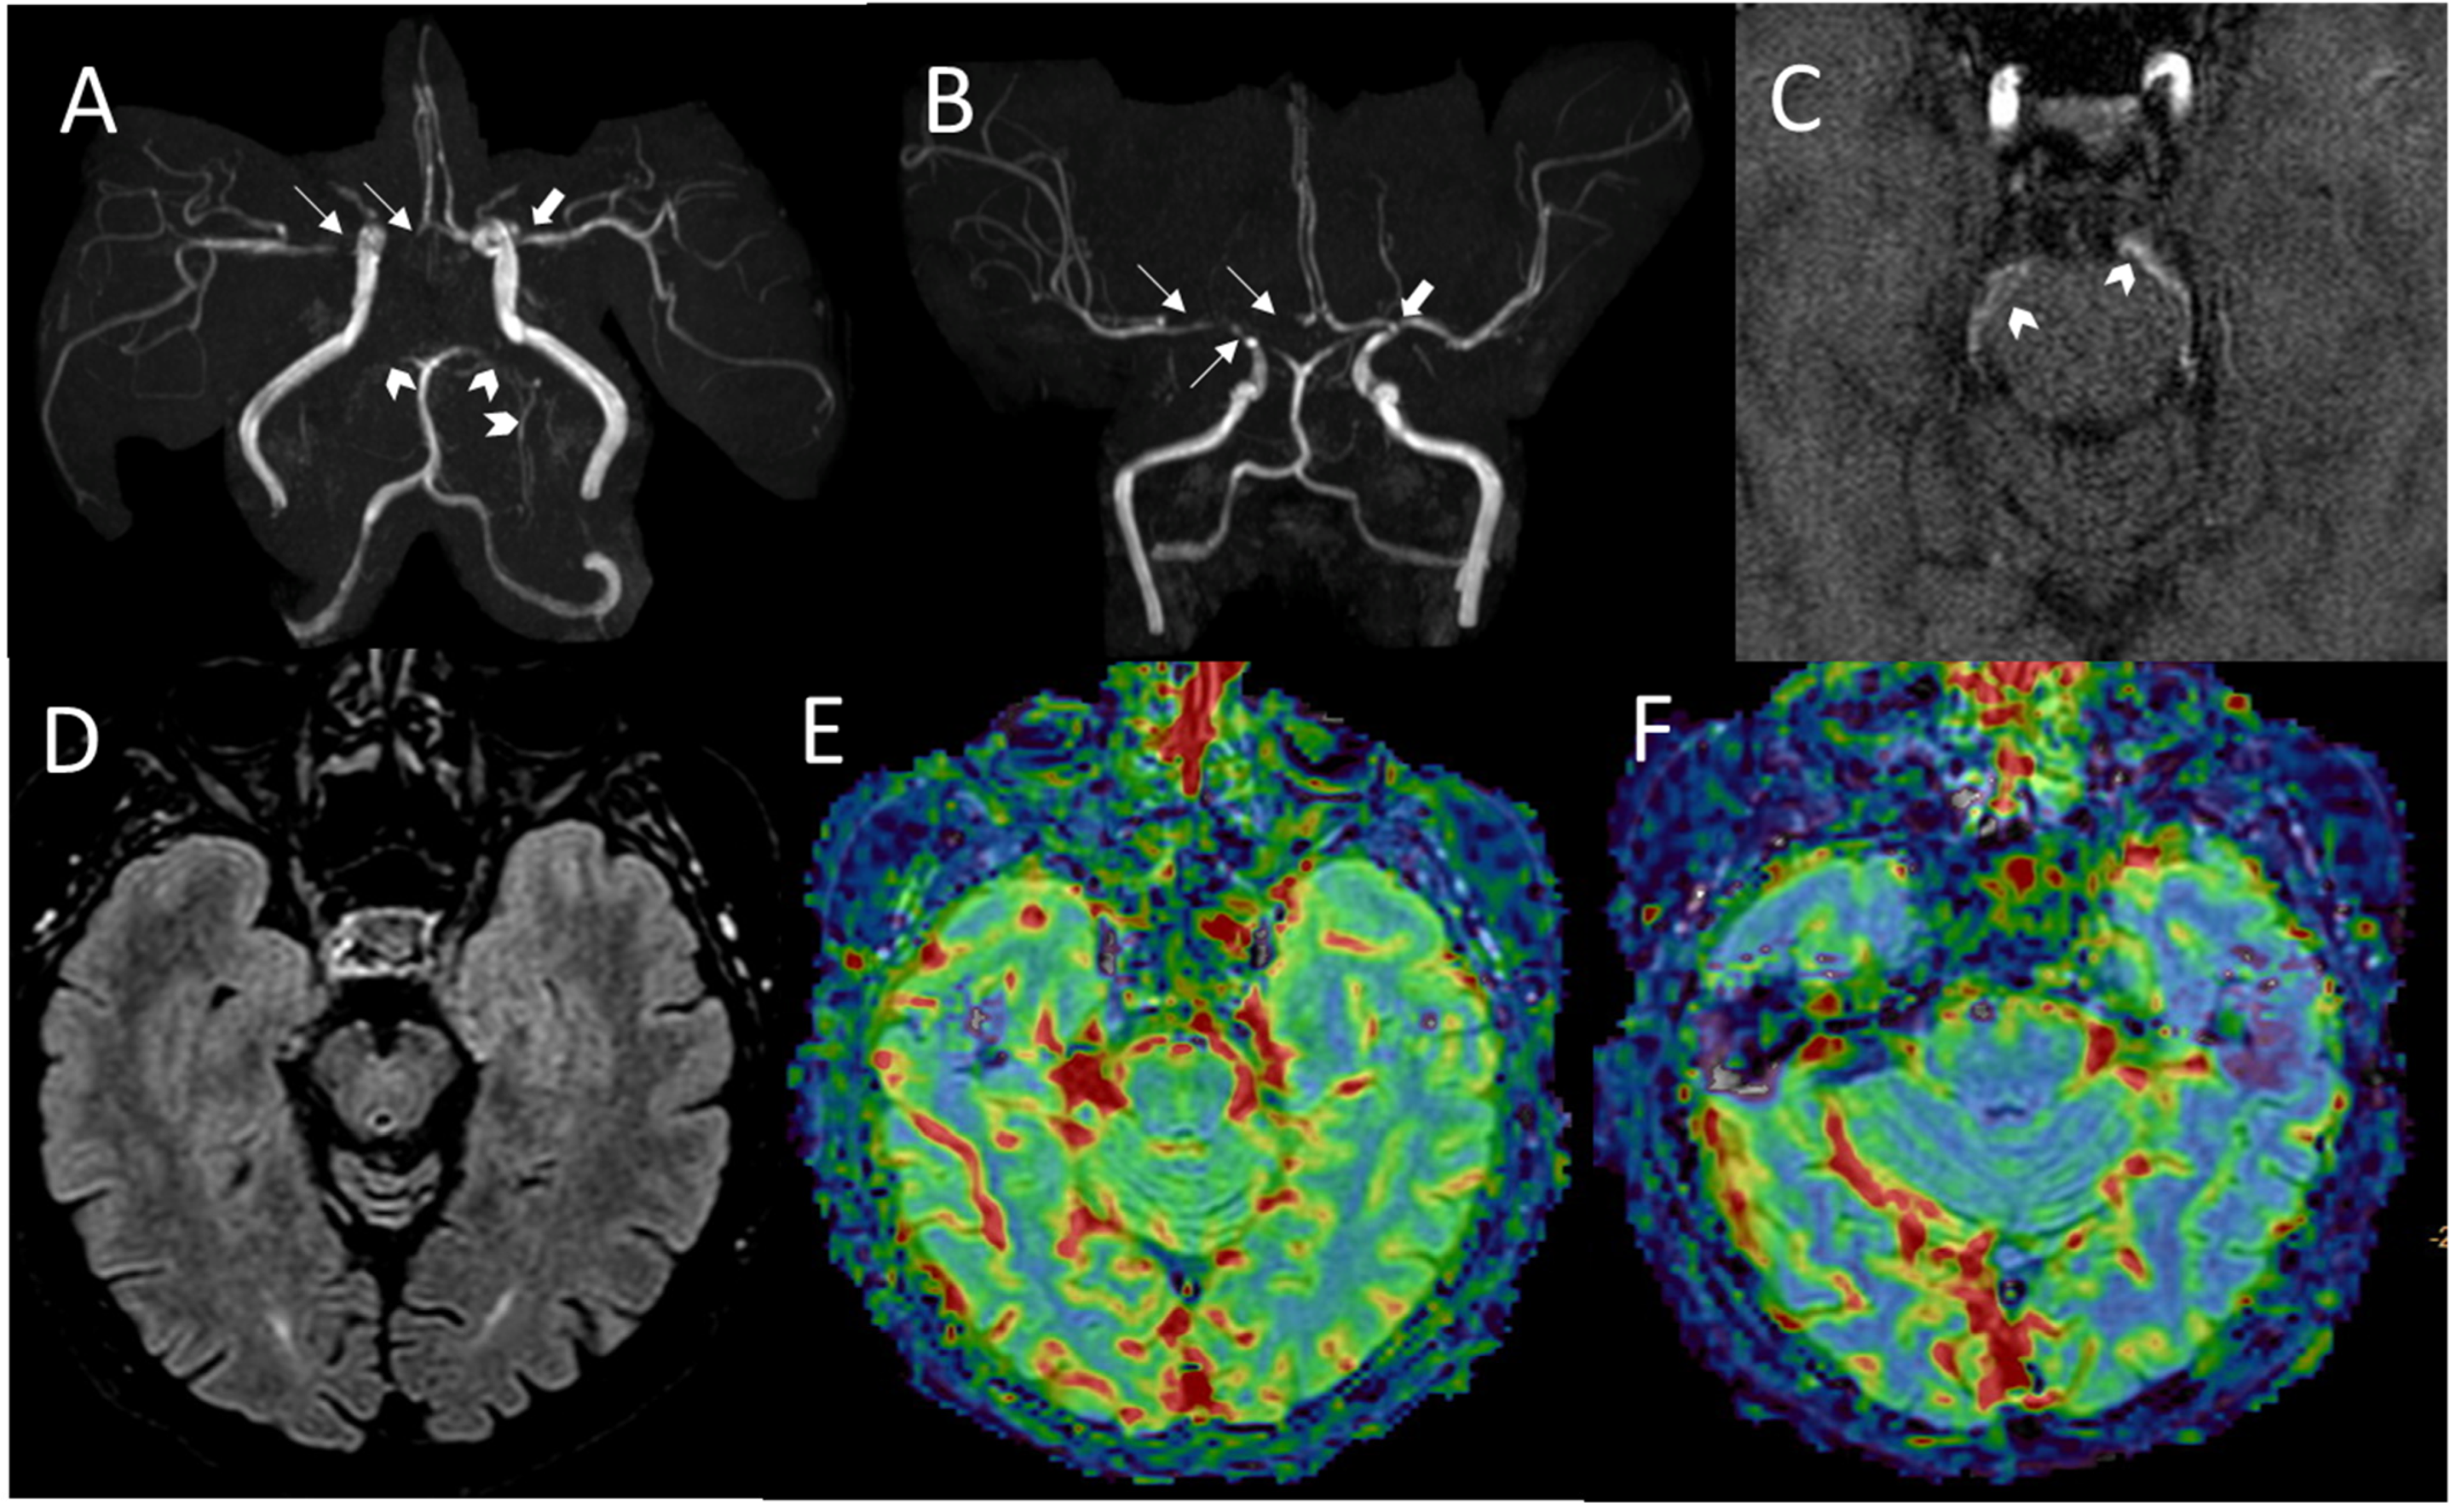

2.1. Family A

2.2. Family B

2.3. Family C